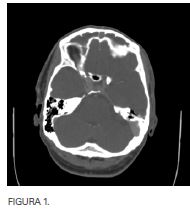

Paciente varón de 39 años sin antecedentes personales de interés que ingresa por sinusitis complicada clínica y radiológica (figura 1) de tres semanas de evolución que presenta cefalea frontal intensa que no mejora con tratamiento antibiótico, corticoideo tópico y sistémico. Tras cinco días de ingreso con tratamiento intravenoso comienza con aumento de la cefalea frontal y fiebre por lo que se realiza nuevo TAC de senos paranasales (figura 2) en el que se aprecia sinusitis frontal y etmoidal bilateral con un pequeño empiema epidural frontal derecho sin aparente dehiscencia ósea de la pared posterior de seno frontal ipsilateral.